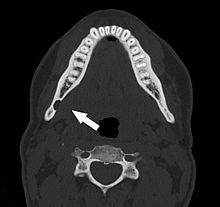

Axial computed tomograph of the same person. The Stafne defect appears as a well corticated 1 cm round defect in the medial cortex of the mandible in the right angle of the jaw (arrowed).

Stafne's defect is usually discovered by chance during routine dental radiography.[4] Radiographically, it is a well-circumscribed, monolocular, round, radiolucent defect, 1–3 cm in size, usually between the inferior alveolar nerve (IAN) and the inferior border of the posterior mandible between the molars and the angle of the jaw. It is one of the few radiolucent lesions that can occur below the IAN. The border is well corticated and it will have no effect on the surrounding structures. Computed tomography (CT) will show a shallow defect through the medial cortex of the mandible with a corticated rim and no soft tissue abnormalities, with the exception of a portion of the submandibular gland. Neoplasms, such as metastatic squamous cell carcinoma to the submandibular lymph nodes or a salivary gland tumour, could create a similar appearance but rarely have such well defined borders and can usually be palpated in the floor of the mouth or submandibular triangle of the neck as a hard mass. CT and clinical exam is typically sufficient to distinguish between this and a Stafne defect. The Stafne defect also tends to not increase in size or change in radiographic appearance over time (hence the term "static bone cyst"), and this can be used to help confirm the diagnosis.[4] Tissue biopsy is not usually indicated, but if carried out, the histopathologic appearance is usually normal salivary gland tissue. Sometimes attempted biopsy of Stafne defects reveals an empty cavity (possibly because the gland was displaced at the time of biopsy), or other contents such as blood vessels, fat, lymphoid or connective tissues. Defects of the anterior lingual mandible may require biopsy for correct diagnosis at this unusual location.[2] The radiolucent defect here may be superimposed on the lower anterior teeth and be mistaken for an odontogenic lesion. Sometimes the defect may interrupt the contour of the lower border of the mandible, and may be palpable. Sialography may be sometimes used to help demonstrate the salivary gland tissue within the bone.